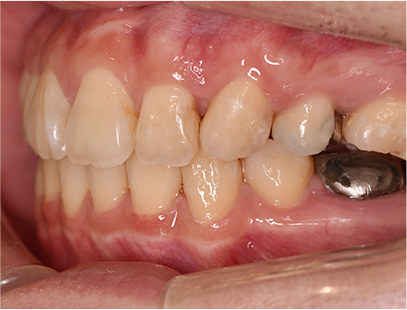

• 左側

• 右側